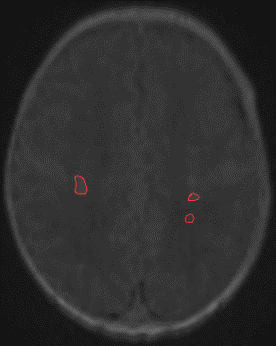

Figure 1: (a) and (b) Manual segmentation of thalami (blue), CVS (green) and PWML (red) in a reconstructed 3D cUS acquisition of a premature infant, (c) 3D cUS manual segmentation and (d) corresponding 3D MRI automatic segmentation of PWMLs (red) in the same premature infant.

Le but de ce stage est d’étudier puis de développer des modèles d’apprentissage automatique pour la détection-segmentation des lésions cérébrales (PWML figure 1) et leur suivi sur plusieurs examens, en utilisant des modèles supervisés pour la segmentation (ex : TransU-Net [2], Swin-UNet [3] ou Mask R-CNN [4]) et entrainés pour chaque temps d’examen (approche statique supervisée). Dans l’idée d’alléger l’annotation du médecin pour chaque structure, on propose d’aborder une approche dynamique semi-supervisée inspirée des méthodes de segmentation de séquences vidéos [5]. Ces méthodes dites VOS (Video Object Segmentation) basées sur les transformeurs ont été développées pour la mise en correspondance des pixels entre l’image (frame) de référence avec l’image cible (Query frame) atteignant de très bonnes performances [5].